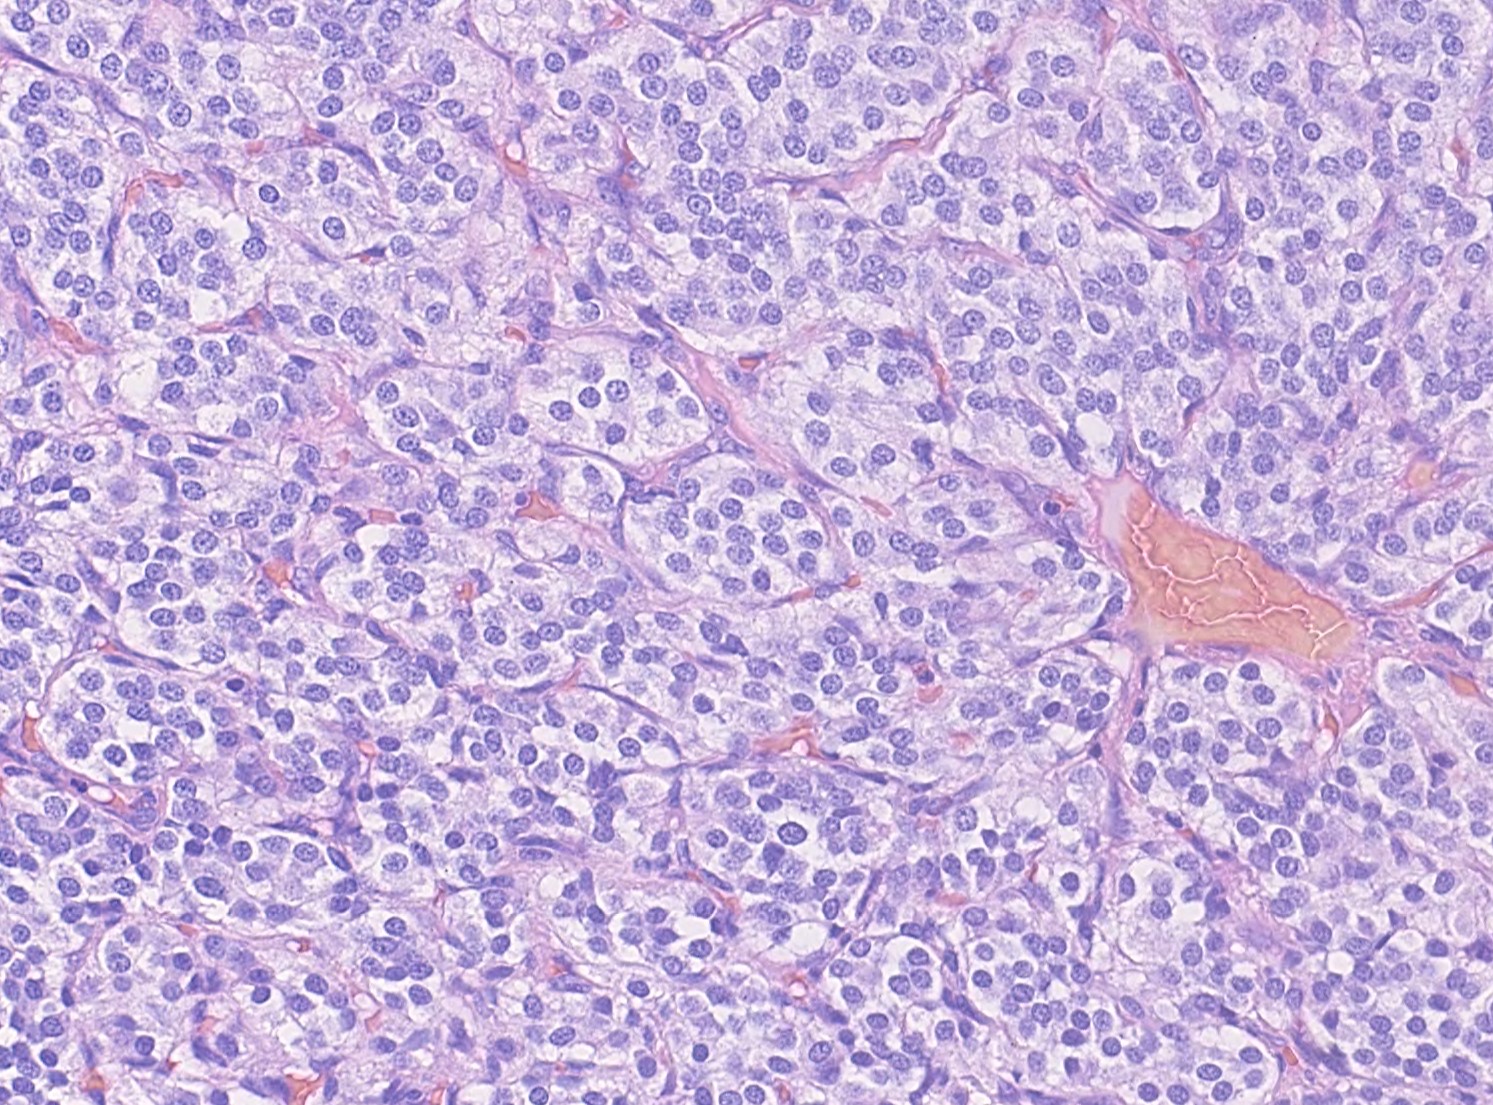

Carotid body paragangliomas are slow growing, well circumscribed tumors with a reddish-brown, firm cut surface. Hemorrhage and cystic degeneration may be seen. On microscopy, nests of oncocytic cells ("zellballen"), often with prominent intranuclear cytoplasmic pseudoinclusions, are surrounded by a fibrovascular network including small spindled sustentacular cells. As demonstrated by this case, an organoid growth pattern is most common in head and neck paragangliomas, but trabecular and solid growth, spindled areas, pigmentation, stromal sclerosis and even amyloid deposition have been described (Head Neck Pathol 2015;9:300). The sustentacular cells stain with S100 and the tumor cells with neuroendocrine markers (synaptophysin, chromogranin, CD56). A reticulin stain will highlight the fibrovascular network. Management is surgical resection (Arch Pathol Lab Med 2014;138:182).

Carotid body paragangliomas are slow growing, well circumscribed tumors with a reddish-brown, firm cut surface. Hemorrhage and cystic degeneration may be seen. On microscopy, nests of oncocytic cells ("zellballen"), often with prominent intranuclear cytoplasmic pseudoinclusions, are surrounded by a fibrovascular network including small spindled sustentacular cells. As demonstrated by this case, an organoid growth pattern is most common in head and neck paragangliomas, but trabecular and solid growth, spindled areas, pigmentation, stromal sclerosis and even amyloid deposition have been described (Head Neck Pathol 2015;9:300). The sustentacular cells stain with S100 and the tumor cells with neuroendocrine markers (synaptophysin, chromogranin, CD56). A reticulin stain will highlight the fibrovascular network. Management is surgical resection (Arch Pathol Lab Med 2014;138:182).